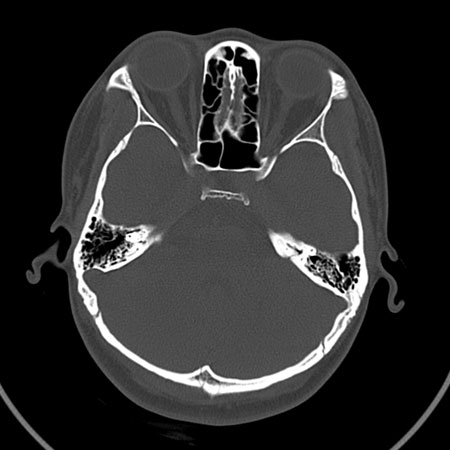

请问各位战友:图示箭头处是否为颅骨骨折?

病史:患者,女,20岁.头部及腹部外伤20分钟.伤后昏迷,无呕吐.头及右侧腰背部疼痛,双侧瞳孔等大,

右肾区叩痛.其它无异常.患者家属否认原有外伤史.

请大家看看是否为颅骨骨折.还是正常变异,或为陈旧骨折.谢谢.

图片未上传完,所见图象示枕骨线样低密度影,边缘锐利,结合外伤史,伤后昏迷,骨折不能除外。

枕骨的线样低密度影锐利、清晰,但正好位于矢状缝的位置,局部无明显软组织肿块,相临及对冲部位脑实质亦无出血及挫裂伤表现。

单就这几层暂不考虑骨折,建议上传完整图片。

枕部锐利透亮线,可以考虑枕骨骨折.

枕骨是单块的,矢状缝是在顶骨而不是在枕骨,枕骨后缘见线状低密度,边缘税利,考虑在骨折存在。

枕后部及左侧颞枕部边缘锐利的线样低密度影,局部软组织无异常,左侧乳突蜂房密度均匀,硬膜下及脑实质内未见出血灶,考虑为正常变异。

枕部锐利透亮线,可以考虑枕骨骨折.左侧枕颞缝。

枕部考虑骨折。一般的颅逢不会跨越板障,楼主所示枕骨断面两侧板障也不连续。

ct 扫描发现枕骨变异一例

患者男,19 岁。因头部外伤就诊。体检:营养、发育良好,五官对称,外观无畸形。右额部见局部皮肤青紫,无皮肤破损。ct 扫描:脑组织及颅外软组织未见异常;骨窗见枕骨中下部,由枕骨内、外隆凸至枕骨大孔处有一线样长约27 mm裂隙(图1、2),宽约1 .0 mm。边缘光滑、硬化,贯穿枕骨内外板。颅骨无

凹陷及移位征象。

讨论: 胚胎学研究证实,枕骨发源于脊椎而不是颅骨,在胚胎形成40 ~ 42 体节时,前部5 个体节形成

枕骨。枕骨基底部和鳞部各有一个骨化中心,还有两个枕骨外侧部[1],分别出现于胚胎的第7 周及第8 周。本例枕骨枕鳞部骨缝可能与枕骨各骨化中心发育障碍有关。经枕骨隆凸至枕大孔处骨缝变异极为罕见,易误诊为骨折,细致观察骨缝边缘是否有硬化和软组织是否肿胀即可与骨折相鉴别。